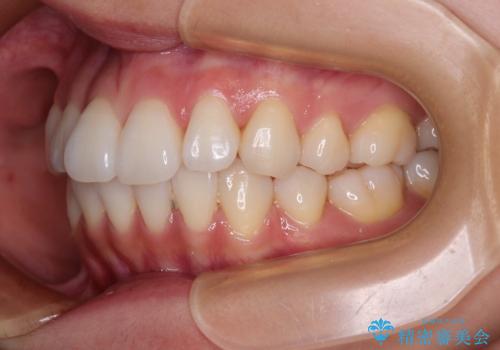

1. 抜歯矯正の軽度後戻りを解消 インビザライン矯正の治療前